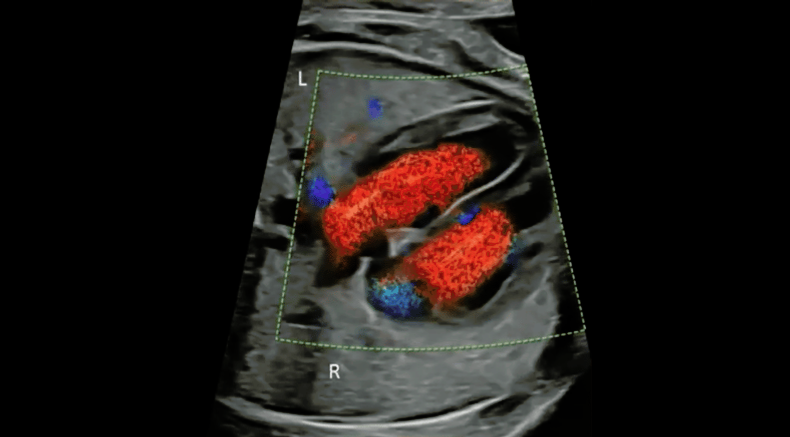

Ultrasound image of the four-chamber view with colour Doppler showing two separate blood inflows into the ventricles during diastole

Carvalho, J.S., Axt-Fliedner, R., Chaoui, R., Copel, J.A., Cuneo, B.F., Goff, D., Gordin Kopylov, L., Hecher, K., Lee, W., Moon-Grady, A.J., Mousa, H.A., Munoz, H., Paladini, D., Prefumo, F., Quarello, E., Rychik, J., Tutschek, B., Wiechec, M. and Yagel, S. (2023)